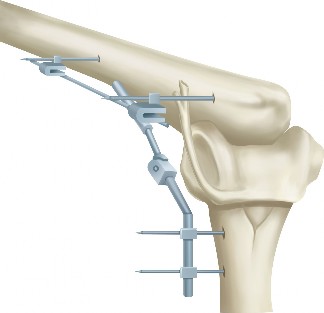

A sophomore, high school wide receiver presents to your clinic at the beginning of his football season. He reports a dislocation event after being tackled; his shoulder was “put back in place” by the on-field athletic trainer. A CT scan taken in the hospital today is shown (Fig. 2–33). He has been recruited by numerous colleges, plans to play at a division 1 school, and is very eager to return to the field.

Figure 2–33

What is the best treatment option for this patient?

Discussion

The correct answer is (E). A large bony fragment (>20%) makes the failure rate with nonoperative treatment (Answers A, B) unacceptably high. This question is meant to illustrate the challenges associated with treating an in-season athlete and highlighting the indications for surgery after a first time dislocation event. Typically, early in a season, providers will initiate an aggressive PT program and try and return athletes to the field within a few weeks so that they can play out the remainder of the season. Towards the end of the season, when there is insufficient time to rehab a patient, one may choose early surgery so that the patient has maximal time to recover prior to the next season. In this case, even though the

patient is extremely motivated to return to the field and has only sustained a single dislocation event, the large bony Bankart lesion behooves surgical treatment. The best option for him would be to have early surgery and have a maximal amount of time to prepare for his senior season. A Latarjet procedure (Answer C) is used for patients with recurrent anterior instability and significant glenoid bone loss, and the Magnuson–Stack procedure (Answer D) is a largely historic procedure that was used for recurrent anterior instability. Objectives: Did you learn...? The common presentation of a patient with shoulder instability?